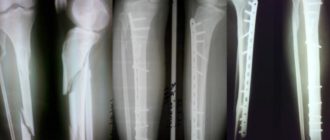

На работе получила травму. Диагноз: закрытый двухлодыжечный перелом правой голени

Ортопед-травматолог

Двухлодыжечный перелом голени Двухлодыжечный перелом — представляет собой травматическое повреждение голеностопного сустава, характеризующееся переломом